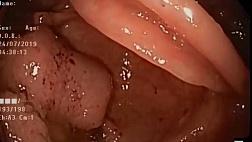

09 июня 2017г. трем больным с различными патологиями желудочно-кишечного тракта были проведены редчайшие операции с применением эндоскопа экспертного класса последнего поколения и эндоУЗИ, привезенными и предоставленными российским филиалом фирмы PENTAX. Руководитель отделения эндоскопии НИИ хирургии и неотложной медицины, СПб ГМУ им. акад. И.П. Павлова, к.м.н. Смирнов Александр Александрович провел мастер-класс с применением диагностических и хирургических эндоскопических методик в этой области. Важно отметить то, что в России подобного рода операции проводят лишь двое специалистов, одним из которых является д-р Смирнов. Камеры, установленные в конференц-зале и операционной позволили в прямом эфире наблюдать за ходом операций, которые в интерактивном порядке освещались Смирновым А.А.

Эндоскопические обследования проводят с помощью цифровой видеоэндоскопической системы последнего поколения — PENTAX Hi-Line HD+ (Япония). Подобный мастер-класс был проведен ранее в октябре 2016г. в МЦ НАИРИ (также организованный российским филиалом фирмы PENTAX).

Эндоскопия - методика исследования внутренних органов при помощи специальной аппаратуры (эндоскопа). Эндоскопия желудочно-кишечного тракта является одним из передовых лучших методов диагностики без хирургического вмешательства, и самым частым методом инструментального исследования пациентов. Исследование осуществляется с помощью эндоскопа, имеющего на одном конце окуляр, который позволяет увидеть картину исследуемого органа, а на другом – камеру, передающую изображение из различных исследуемых областей желудочно-кишечного тракта. Опытные специалисты с его помощью смогут обнаружить проблему на самой ранней стадии развития и своевременно назначить необходимое лечение.

Первая пациентка: D-s - опухоль поджелудочной железы. Было проведено эндоУЗИ и пункционная биопсия опухоли.

Вторая пациентка с ахалазией пищевода, в стадии компенсации. Была проведена эзофагогастродуоденоскопия (по ходу была определена эрозия: взят материал для биописии).

Третий пациент был обследован тем же методом по поводу образования в желудке (больному было предложено динамическое наблюдение).